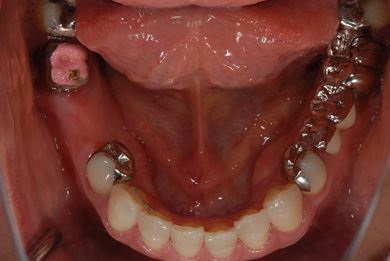

| 主訴 | ブリッジの支えとなっている歯が虫歯になり、ブリッジが難しくなったため、インプラントか義歯かの相談で来院。 | ||||||||||||||||||||||||||||||||

| 治療方針 | 抜歯と同時にインプラント治療を行い、治療期間を短縮する。 | ||||||||||||||||||||||||||||||||

| 治療内容 | インプラント4本(抜歯即日スピードインプラント治療)、ハイブリッドセラミッククラウン6本 | ||||||||||||||||||||||||||||||||